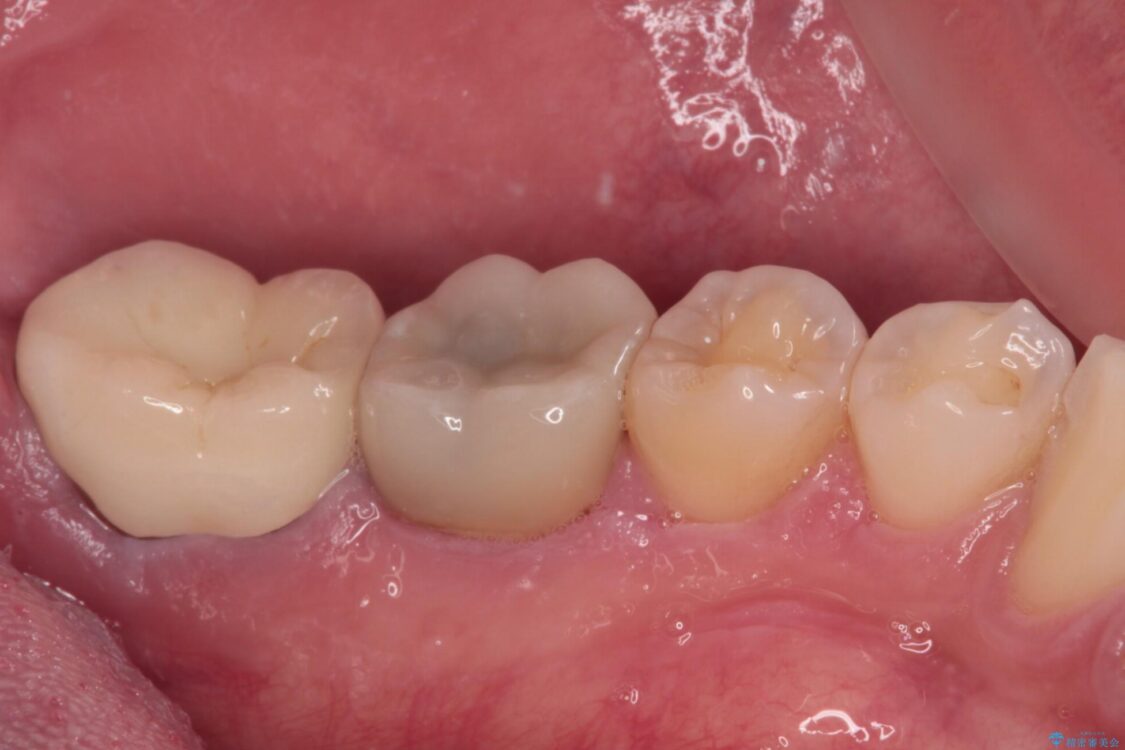

• 海外赴任前に治したい 割れてしまった奥歯のオールセラミッククラウン 治療後画像